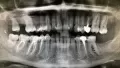

Попала к девушке со стажем работы 1 месяц. Мне удаляли нервы, но не смогли полноценно запломбировать зуб. Только один из каналов вроде запломбировали, т.к. из канала шла кровь, и они не могли её остановить. Прижигали мне там что-то по 10 раз. Поставили временную пломбу, а под нее вату. На следующий день тоже самое, на помощь молодому врачу подключилась врач со стажем. Она посверлила еще и нашла еще один канал. Опять прижигали. Шептались постоянно, я услышала фразу про две перфорации. Послали на рентген. Следующий прием только через 3 дня. К ней точно не пойду, уже нет доверия. Это была стоматология по ОМС. Пойду в платную стоматологию, может, спасут зуб.

По снимку, определить о какой перфорации шептались Ваши врачи, не представляется возможным.